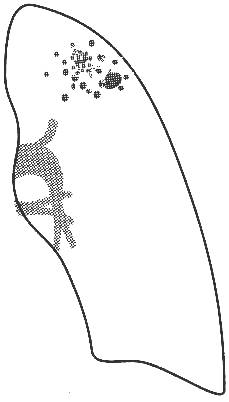

Рис. 4 Рентгенограмма ОГК и схема к ней левого легкого.

В

апикальном отделе S1–2 левого легкого определяется обогащенный легочный рисунок

за счет множественных полиморфных преимущественно среднеочаговых теней,

склонных к слиянию с нечеткими контурами; здесь же имеются плевроапикальные

наслоения. Корни легких структурны, не расширены. Купол диафрагмы четкий,

синусы свободны.

Заключение:

Очаговый туберкулез в S1–2 левого легкого в стадии инфильтрации.